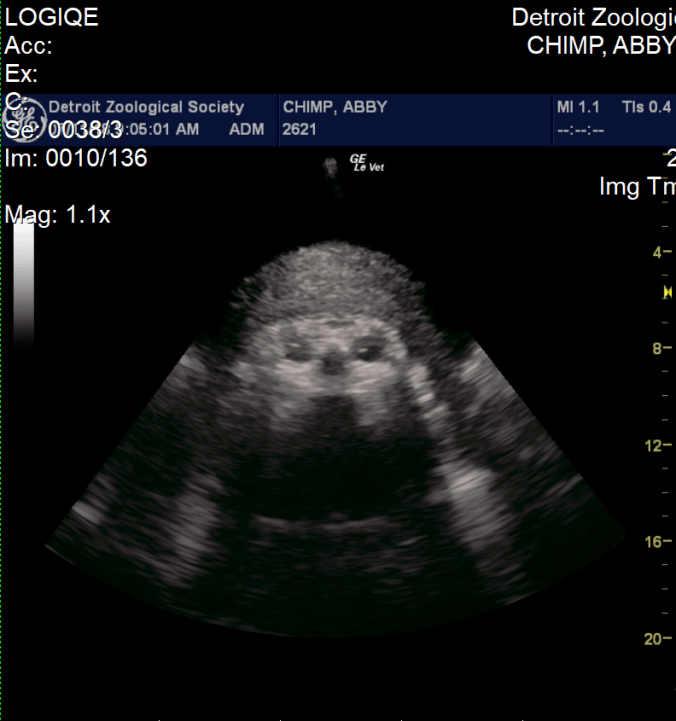

Abby was a cooperative patient and always appeared excited to see us. She would prop herself on a ledge and eat peanuts during each exam, allowing the peanut shells to pile up on her growing belly. There are limits to the ways we can position the probe, and we were not always able to get every measurement at every visit. In the early months, we were able to measure the length of the fetus from the crown to the rump; as the baby grew, we measured the circumference of the head and abdomen and length of the long bones, including the femur and humerus. We were also able to see the position of the fetus and measure the heart rate. With each exam, we added data to our growth charts, and were pleased to see steady growth and development. We also became increasingly confident that the baby was a girl.

Abby is the third chimpanzee mom that has allowed us to conduct obstetrical ultrasounds, and since 2008 we have been able to collect measurements from three pregnancies, including youngsters Ajua and Akira. Using these measurements and data from two scientific publications, we were able to make a solid prediction of Abby’s due date – July 14, the date of the first annual World Chimpanzee Day! As this date approached, animal care staff began round-the-clock checks to look for signs of labor. Just three days before the due date, we performed a final ultrasound exam. We were pleased to see that the baby was still growing according to expectations. We could see her face and watch her open and close her mouth and wiggle her arms and legs. Most importantly, we could see that the baby had a strong heartbeat and was positioned with her head down, which is the correct position for a normal delivery.